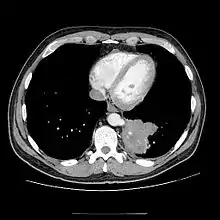

Chest CT showing pulmonary sequestration

• CT scans have 90% accuracy in the diagnosis of pulmonary sequestration.

• The most common appearance is a solid mass that may be homogeneous or heterogeneous, sometimes with cystic changes.

• Less frequent findings include a large cavitary lesion with an air-fluid level, a collection of many small cystic lesions containing air or fluid, or a well-defined cystic mass.

• Emphysematous changes at the margin of the lesion are characteristic and may not be visible on the chest radiograph.

• CT technique for optimal depiction of lesions by using state-of-the-art volumetric scanning requires a fast intravenous (IV) contrast injection rate and appropriate volume and delay based upon size.

• Multiplanar and 3D reconstructions are helpful.